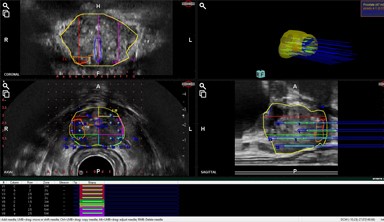

当院では、最新システム「ARIETTA 65 IntuitiveFusion」を導入しています。

MRIで撮影した高解像度画像とリアルタイムの超音波画像をコンピューター上で融合し、どの位置を採取すればよいかを画面上で確認できる仕組みです。

これにより、狙った病変を正確に採取でき、がんの診断率が向上します。

MRI融合生検では、針を刺す位置が画面上にガイド表示され、まるでバックモニターのように、経験に頼らず確実に目標をとらえられるようになります。